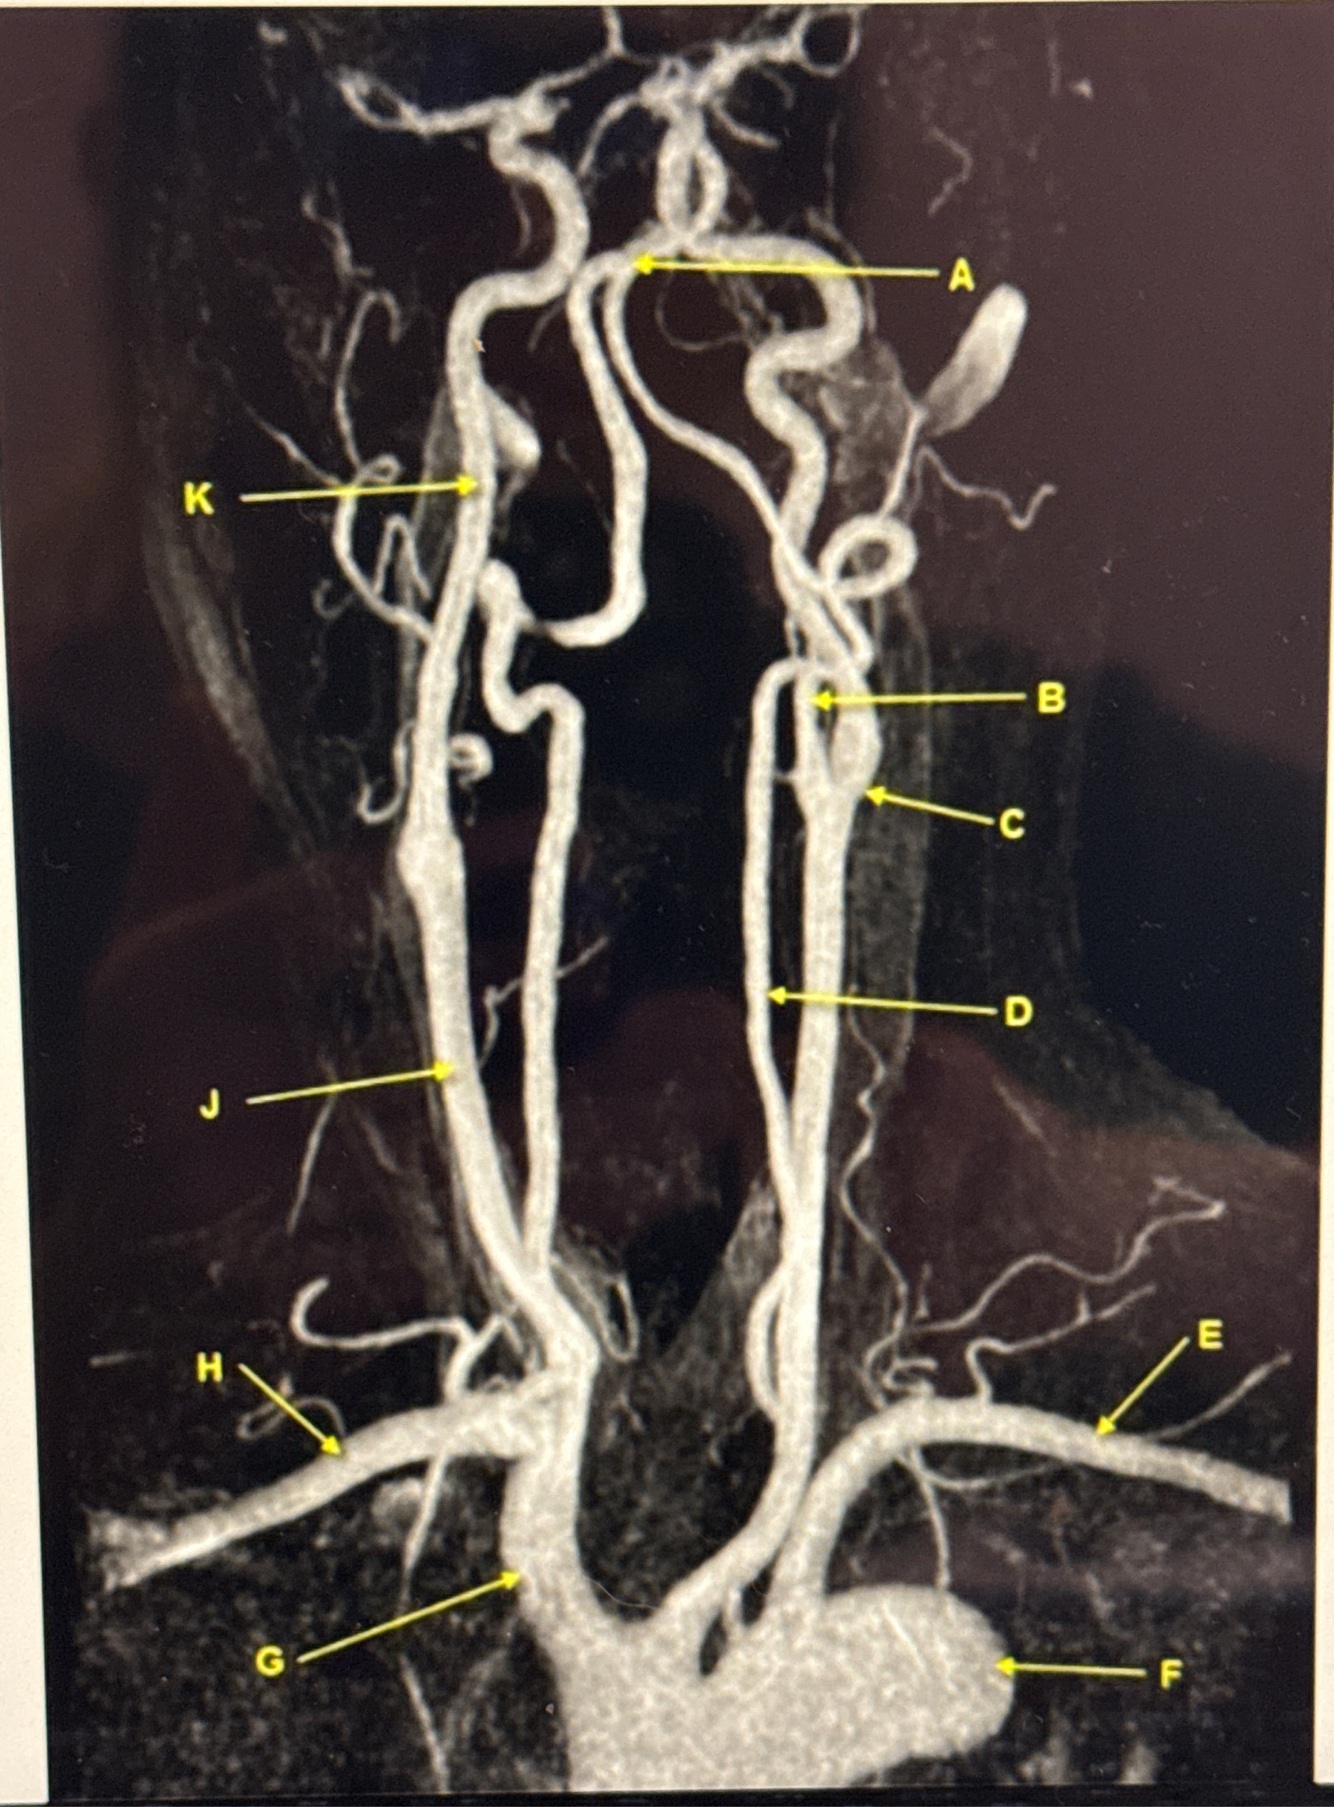

Q

MRA EXTRACRANIAL CIRCULATION

Letter J points to

Letter A points to the

Letter E points to the

Letter K points to the

Letter C points to the

VertebroBasilar junction

Letter B points to the _______ and letter D points to the ______

B. External carotid artery

D. Vertebral artery

Letter E points to the _____ and letter F points to the _____

E. Left subclavian artery

F. Thoracic aorta

Letter G points to the _____ , letter H points to ______ and letter J points to the

G. Brachiocephalic

H. Right subclavian artery

J. Common carotid artery

Letter K points to the ________,

K. Internal carotid artery